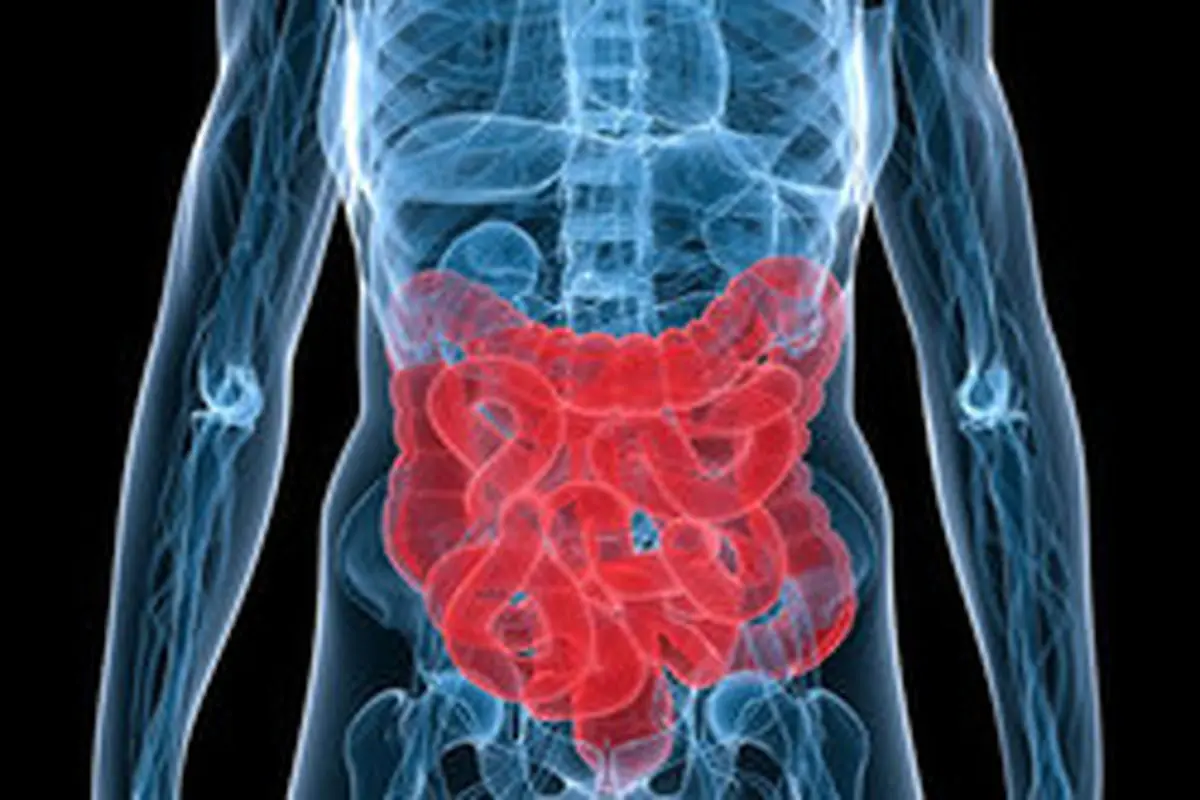

۷ توصیه برای بهبود سلامت رودهها

پارسینه: چندین گونه از میکروبها نقش مهمی در حفظ میکروبیوم (ریز اندامگان همزیست) رودهها دارند و راه های زیادی از خوردن غلات کامل گرفته تا تغذیه با شیر مادر برای حفظ آنها وجود دارد.

میکروبهای روده برای حفظ سلامت رودهها و دستگاه گوارش بسیار مفیدند و در نهایت منجر به حفظ سلامت عمومی بدن میشوند.

در این مقاله به نقل از روزنامه گاردین هفت راهکار برای بهبود سلامت رودهها عنوان شده که به شرح زیر است: